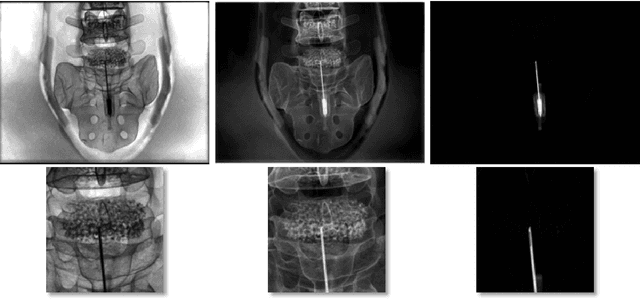

Abstract:Involuntary motion during weight-bearing cone-beam computed tomography (CT) scans of the knee causes artifacts in the reconstructed volumes making them unusable for clinical diagnosis. Currently, image-based or marker-based methods are applied to correct for this motion, but often require long execution or preparation times. We propose to attach an inertial measurement unit (IMU) containing an accelerometer and a gyroscope to the leg of the subject in order to measure the motion during the scan and correct for it. To validate this approach, we present a simulation study using real motion measured with an optical 3D tracking system. With this motion, an XCAT numerical knee phantom is non-rigidly deformed during a simulated CT scan creating motion corrupted projections. A biomechanical model is animated with the same tracked motion in order to generate measurements of an IMU placed below the knee. In our proposed multi-stage algorithm, these signals are transformed to the global coordinate system of the CT scan and applied for motion compensation during reconstruction. Our proposed approach can effectively reduce motion artifacts in the reconstructed volumes. Compared to the motion corrupted case, the average structural similarity index and root mean squared error with respect to the no-motion case improved by 13-21% and 68-70%, respectively. These results are qualitatively and quantitatively on par with a state-of-the-art marker-based method we compared our approach to. The presented study shows the feasibility of this novel approach, and yields promising results towards a purely IMU-based motion compensation in C-arm CT.